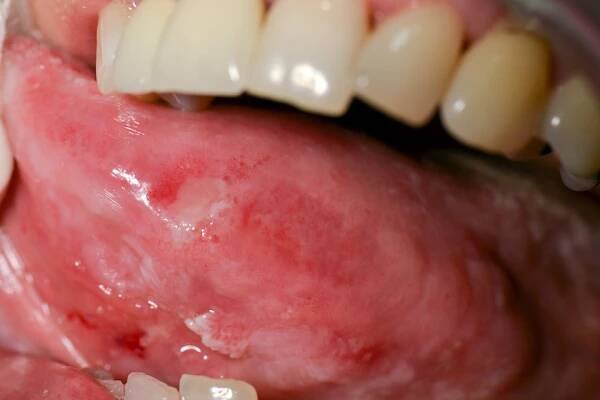

Pacient se zhoubným nádorem (spinocelulární karcinom), který je viditelný na povrchu pod jazykem. Tento vysoce maligní nádor je nejzávažnější typem rakoviny úst. Vřed může být prvním příznakem, časem se může rozšířit na dásně, dolní čelist, lymfatické uzliny.

Nádory jazyka se řadí k onemocněním ústní dutiny. Nádory jazyka se dělí na dvě hlavní skupiny - nádory nezhoubné (benigní) a zhoubné (maligní) neboli také mezi…

Rakovina ústní dutiny je zhoubný nádor, které obvykle vzniká v ústní sliznici. Nádor se přitom může vyskytnout v kterékoli oblasti ústní dutiny – například ...